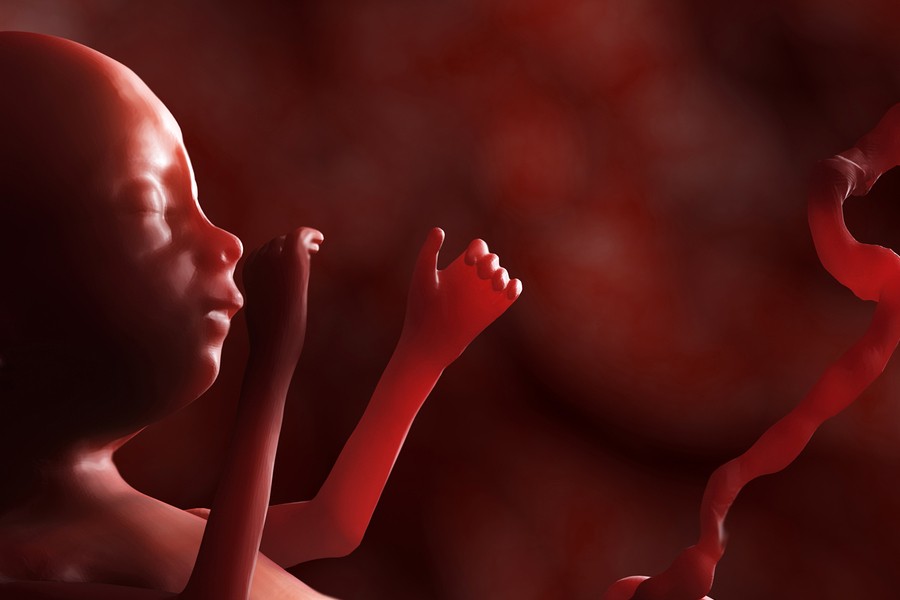

La espina bífida es un defecto congénito que se presenta cuando el tubo neural —estructura que formará el cerebro y la columna vertebral— no logra cerrarse adecuadamente durante el primer periodo del embarazo. El neurocirujano pediatra del INPer, Rolando Jiménez Guerra, explicó que este proceso ocurre en una etapa muy temprana de la gestación, “cuando muchas mujeres ni siquiera saben que están embarazadas”.

En México, el diagnóstico oportuno suele realizarse entre las semanas 18 y 20 mediante ultrasonido estructural, idealmente realizado por especialistas en medicina materno-fetal. Este estudio permite determinar si el producto es candidato a cirugía fetal, la cual debe efectuarse antes de la semana 26. Cabe señalar que el INPer es uno de los centros nacionales que ofrece esta opción terapéutica, con técnicas abiertas o de mínima invasión.

Jiménez Guerra destacó que, en los últimos nueve años, el instituto ha atendido alrededor del 10 por ciento de los casos de espina bífida registrados a nivel nacional. Asimismo, destacó que actualmente, el 50% de las cirugías ya son fetales, lo cual mejora significativamente la posibilidad de las y los pacientes de caminar de manera independiente.